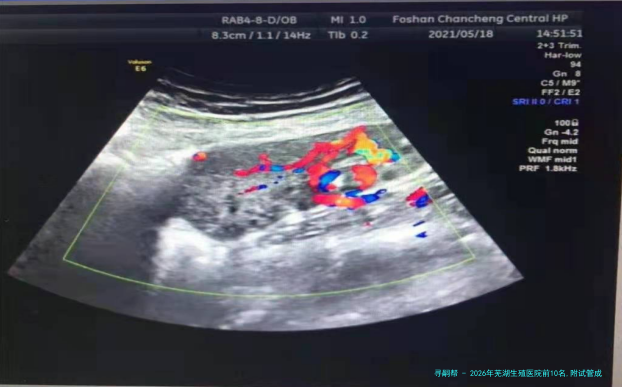

2026年芜湖生殖医院前10名,附试管成功率较高的医院